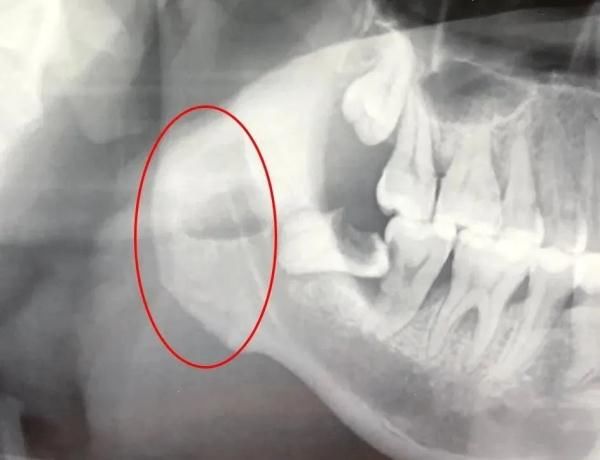

一颗烂掉的智齿发炎十多天,引发颌面部多间隙感染,炎症向下扩散至颈部及前胸,余先生在武汉大学口腔医院接受切排引流手术并拔除智齿后,被送入ICU重症监护室24小时监护。

急诊科副主任医师赵丹、创伤外科副主任医师吕坤接诊后,通过口腔检查和CT辅助检查,诊断他为颌面部间隙感染,建议他立即住院手术治疗,可余先生放不下工期,只请医生做了简单处理,便回家了。

“患者血检报告单中,白细胞数值远超过正常值,感染正在向颈、胸部扩散,引起了胸部疼痛表现,而他空腹血糖指标高达14.25mmol/L、尿糖3+,之前可能存在未察觉的糖尿病。”

吕坤指出,患糖尿病的病人抵抗力较差,身体组织和血液里糖分较高,比普通人更容易引发炎症的感染和扩散,再不手术排脓,恐怕颈部肿胀加重压迫呼吸,向下引发纵膈脓肿、败血症等危及生命。

【 重症监护室|智齿发炎“放倒”男子,拔牙后住进ICU】7月1日,余先生接受手术。术前,麻醉医生先给他注射胰岛素,将血糖尽量控制在全麻要求范围内;随后,吕坤为余先生拔掉发炎的智齿,将颌面颈部多个间隙里的脓肿切开引流。